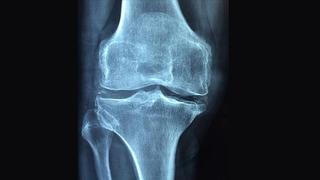

Osteoporoz (Kemik Erimesi) Haberleri